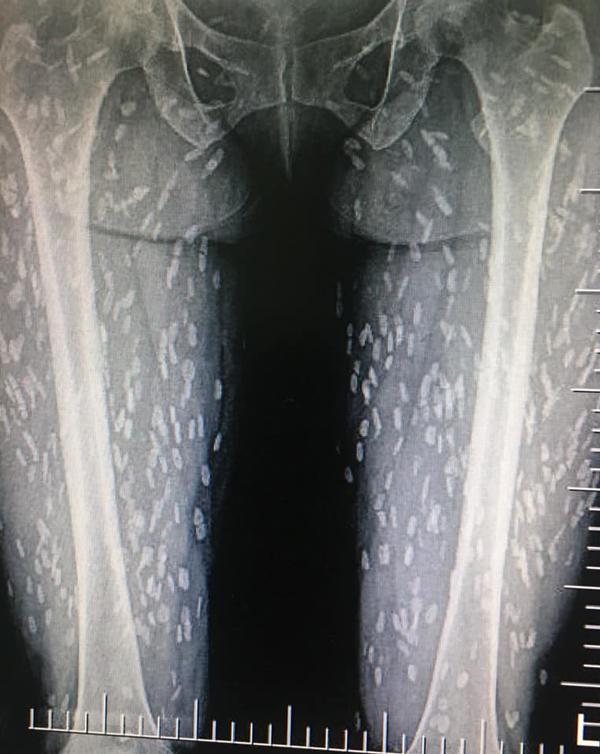

Sau khi chụp X-quang, thấy khắp cơ thể đặc biệt đầy những đốm trắng lạ kỳ. Bác sĩ khi nhìn vào cũng vô cùng kinh ngạc và cho biết đây là những ký sinh trùng đang nằm trên khắp cơ thể nữ bệnh nhân, đặc biệt là phần chân.

Bác sĩ cũng cảnh báo nếu toàn bộ ký sinh trùng này không được loại bỏ thì chỉ một thời gian ngắn nữa, nó có thể gây suy hô hấp hoặc thậm chí tử vong.

Loại ký sinh trùng này được xác định là ấu trùng của sán dải heo hay sán dải lợn. Những nang ấu trùng nhiễm vào não, cơ hoặc các mô khác có thể gây ra các cơn động kinh khởi phát tuổi trưởng thành.